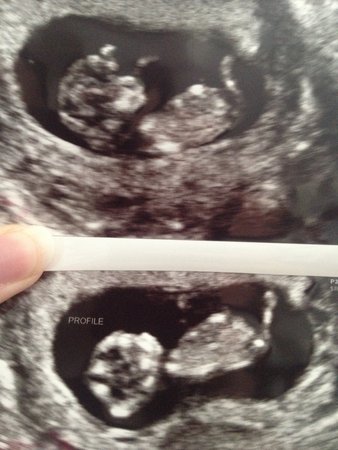

Hope that works this is my first post :) I have two boys already and looking forward to a healthy girl!

No nub in either pic :(